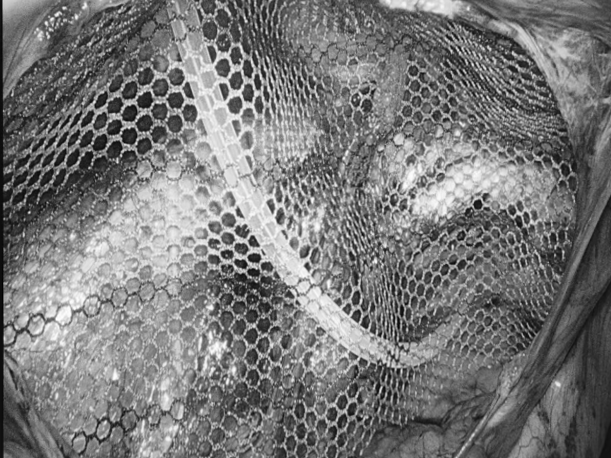

为更好地服务广大患者,贵州航天医院知名肛肠外科专家高大勇教授,每周二上午将固定坐诊贵州航天医院普外科。 坐诊信息 时 间:每周二上午(8:00-11:30) 地 点:贵州航天医院门诊部106诊室(普外科门诊) 挂号通道: 1.门诊大厅或诊室自助挂号缴费机。 2.门诊挂号缴费窗口。 3.贵州航天医院微信公众号预约挂号。 专家简介 高大勇 普外科(肛肠外科)学科带头人、名誉主任,主任医师、教授 临床擅长:对中西医结合诊治肛肠学科各种常见病、多发病及疑难杂症等具有丰富的临床经验。 原遵义市第一人民医院(遵义医科大学第三附属医院)、遵义市中医院肛肠科主任。中华中医药学会肛肠分会常委,全国中医肛肠学科名专家,中国健康促进与教育协会肛肠分会常委,中国康复医学会肛肠疾病康复专业委员会常委,中国民间中医医药研究开发协会肛肠分会副秘书长,中国医师协会中西医结合肛肠医师专业委员会常委,国家二级心理咨询师,贵州省第一批中医名医工作指导老师,遵义市名中医,遵义市肛肠学会会长,遵义市肛肠质控中心名誉主任,遵义市中西医结合学会名誉会长,遵义市健康科普专家,原贵州省中西医结合学会肛肠分会副主任委员、贵州省中医肛肠质控中心副主任、遵义市医学会医疗鉴定委员会专家、遵义市卫生系列高评委。发表论文30余篇,主编和参编医学著作5本,主持省级科研课题2项、市级科研课题2项、院级科研课题1项。 贵州航天医院 普外科简介 基本情况 贵州航天医院普外科成立于1968年,前身属于航天部O61基地3417医院外一科,1998年3417医院、3427医院合并后更名为普外科,下设胃肠外科、肛肠外科2个亚专业科室,拥有在全市较为先进的专科设备和技术,是中国疝病专科联盟单位,贵州医科大学附属医院胃肠外科专科联盟单位。开放床位40张,配备医护人员21人。 专科特色技术 普外科致力于胃肠及肛肠疾病的外科临床诊治及科研,以腹腔镜微创外科技术为本,形成以快速康复治疗胃肿瘤、结直肠肿瘤、小肠肿瘤、直肠脱垂、肥胖病、急腹症、各类疝、痔、瘘等专科特色,同时注重胃肠疾病尤其是结直肠恶性肿瘤的基础研究和临床转化研究,总体诊断和治疗水平在区域同级医院居于领先水平。 开展手术:腹腔镜下胃癌根治术,腹腔镜下袖状胃切除术,腹腔镜下胃肠道间质瘤切除术,腹腔镜下结、直肠癌根治术,胃癌、结直肠癌的精准治疗,腹腔镜下小儿疝气、成人疝修补术,腹腔镜下阑尾手术,内痔的硬化注射治疗及痔疮的微创治疗:ATH、PPH、TST,直肠脱垂的各种手术治疗,难治性伤口VSD技术,鼻胃肠管、肠梗阻导管置入术,肛肠术后间歇性导尿技术,并引进了中医适宜技术,也为各种化疗患者提供输液港安装,提高患者就医体验。 腹腔镜下腹股沟疝 无张力修补术 腹股沟疝里金斯坦(Lichtenstein)手术 PPH微创术治疗环状混合痔 黏连性或炎性肠梗阻-肠梗阻导管 腹腔镜袖状胃切除 腹腔镜阑尾切除术 腹腔镜阑尾肿瘤切除术 腹腔镜下结肠癌根治术 科室诊疗范围 胃肿瘤、结直肠肿瘤、小肠肿瘤、肥胖症、各类急腹症、腹部外伤、腹壁疝、便秘、直肠脱垂、痔疮、肛瘘、肛裂等胃肠、肛肠外科疾病。 END